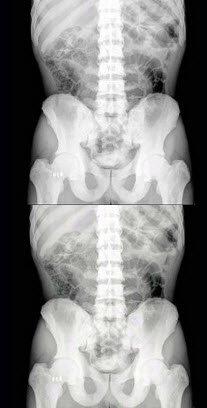

141、单项选择题

女,根据其正常骨盆影像图像,判断其最可能的年龄()

A.53岁左右

B.13岁左右

C.73岁左右

D.33岁左右

E.63岁左右